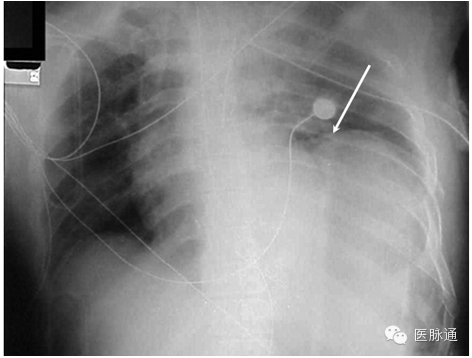

纵隔积气是指纵隔结构中存在游离气体。纵隔积气最常见于食道或相邻肺泡的创伤或医源性损伤。胸片中,游离气体可能形成解剖结构的轮廓。常见表现包括形成心脏影像的透X光细线轮廓(图4白色箭头),纵隔内纵向走形的气体,支气管壁双影征,或右侧肺动脉周围透光区域(即“动脉周围戒指征”)。在侧位胸片上胸骨后间隙最易检测到气体。纵隔积气的气体是固定的且不会移动到最高。

图4